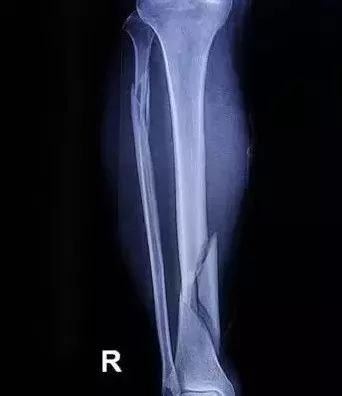

胫腓骨骨折 |

8-10周 |

骨折通常可分为外伤性骨折和病理性骨折两大类。

骨的再生能力很强,经过良好复位后的外伤性骨折,一般在3~4个月或更长一些时间内,可完全愈合。骨外、内膜中骨母细胞的增生和产生新生骨质是骨折愈合的基础。骨折后经血肿形成、纤维性和骨性骨痂形成以及骨痂改建的过程而完全愈合,使骨在结构和功能上恢复正常。

局部血液供应:如果骨折部血液供应好,则骨折愈合快,如肱骨的外科颈(上端)骨折;反之,局部血液供应差者,骨折愈合慢,如股骨颈骨折。骨折类型也和血液供应有关,如螺旋形或斜形骨折,由于骨折部分与周围组织接触面大,因而有较大的毛细血管分布区域供应血液,愈合较横形骨折快。

骨折断端的状态:骨折断端对位不好或断端之间有软组织嵌塞等都会使愈合延缓甚至不能接合。此外,如果骨组织损伤过重(如粉碎性骨折),尤其骨膜破坏过多时,则骨的再生也较困难。骨折局部如出血过多,血肿巨大,不但影响断面的接触,且血肿机化时间的延长也影响骨折愈合。